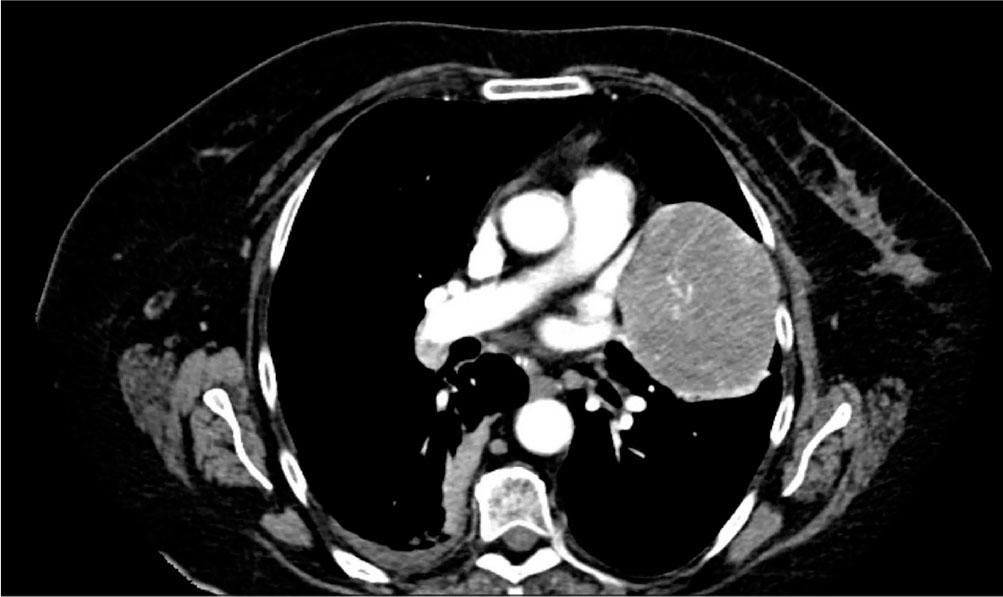

Figure 1.